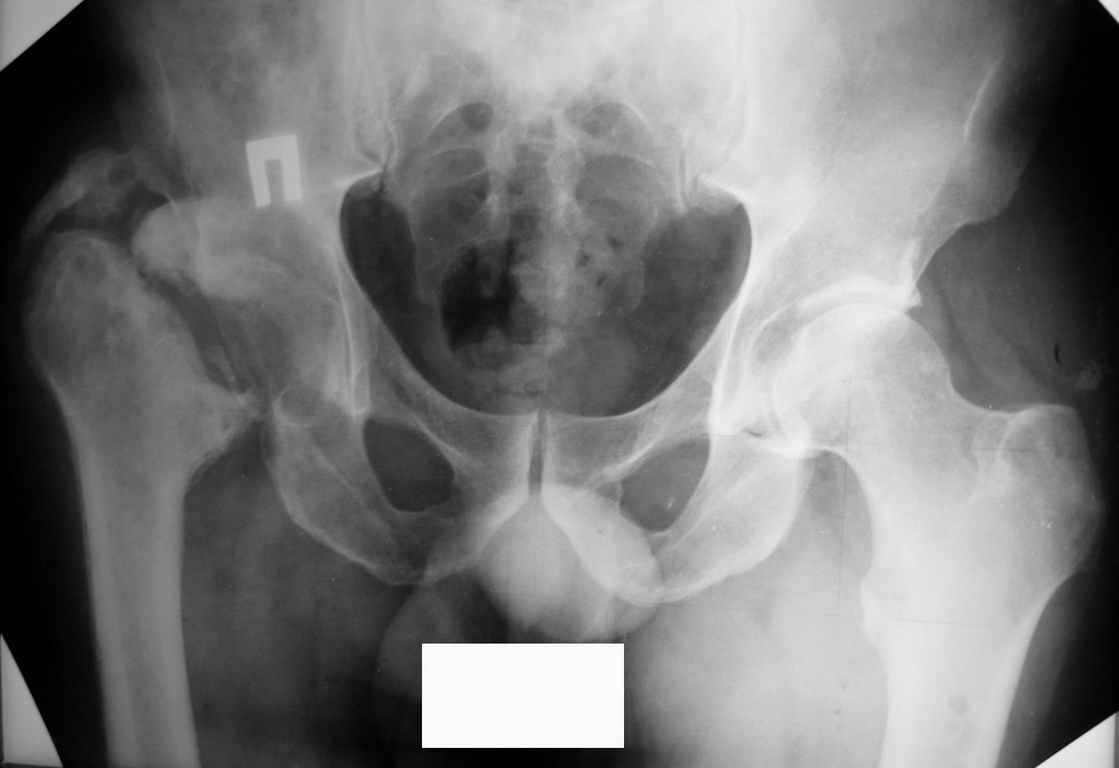

Уважаемые коллеги, прошу высказать ваши мнения по представленному случаю. Пациент - мужчина около 50лет после перенесенной год назад тяжёлой сочетанной травмы.

Был оперирован, среди прочего - остеосинтез DHS-фиксатором чреcшеечного перелома правого бедра, DCS-фиксатором остеосинтез оскольчатого чрезмыщелкового перелома левого бедра. Однако, в связи с развитием гнойного коксита были вынуждены убрать DHS-фиксатор и головку. Гнойный свищ правого тазобедренного сустава закрылся сразу после операции. Из-за вторичного смещения и поломки винтов пришлось удалить DCS-фиксатор и сращивать левое бедро внешней иммобилизацией. Прошло чуть более года. Пациент ходит с опорой на обе ноги,пользуется палочкой. Справа относительное укорочение 3см. Слева варус 33гр., тугой ложный сустав н/3бедра. Движения в коленных суставах почти в полном объёме.Перед нами встали вопросы, с чего начать? Протезирование правого ТБС? Восстановление опорности левой конечности? Воспользоваться-ли для этого интрамдулярным остеосинтезом гвоздём с блокированием с ретроградным введением? Стараться при этом восстановить полностью длину, или оставить на потом, на аппаратное решение? Или сразу попытаться использовать аппарат Илизарова? Но боимся потерять колено? Вопросов много.С благодарностью выслушаем все мнения.Заранее спасибоРахматуллин Ринат НургаяновичГКБ N 13 г.Уфа.